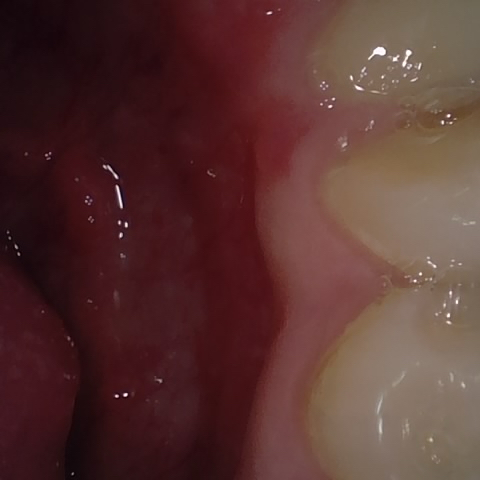

Image 301 / 400

NHD20794

Annotated as "Good"

Original Image Rendering Image